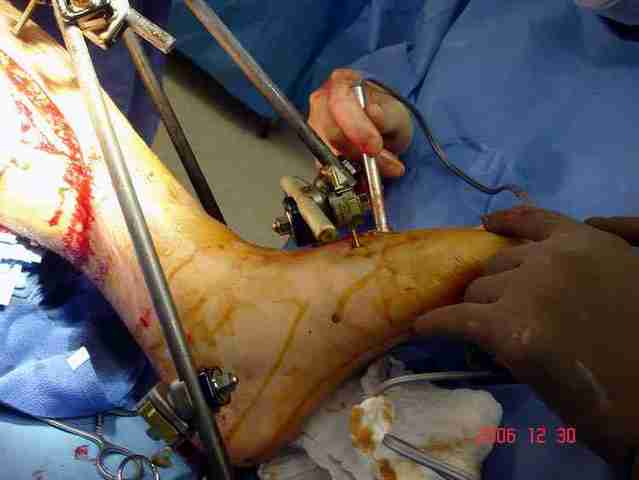

Сравнительный повторный мониторинг на компартмент синдром, на голени утром давление поднялось до 70 мм, когда послеоперационные были около 30мм.

Срочная фасциотомия на всех 4 компартментах: латерально и медиально,

кстати было достаточно только латеральной фасциотомии, чтобы услышать на допплере пульсацию,

на бедре измерения не подтвердили подозрения на компартмент синдром и рана была закрыта вакуумной губкой (wound VAC).